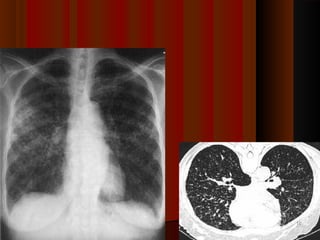

Commonly done test for diagnosis of PTBCommonly done test for diagnosis of PTB

- Sputum examination (3 samples)Sputum examination (3 samples)

- Chest X-RayChest X-Ray

- Mantoux test – screening test (tuberculin test)Mantoux test – screening test (tuberculin test)

- Study of pleural fluid in case of pleural effusion.Study of pleural fluid in case of pleural effusion.